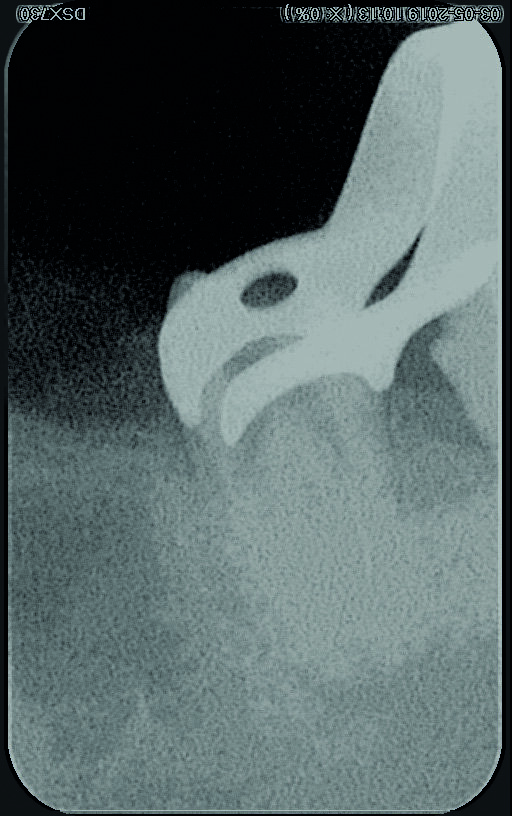

Une femme de 44 ans, sans antécédents médicaux particuliers, nous est adressée pour le retraitement endodontique de sa première molaire inférieure gauche qui cause une douleur depuis une semaine. La dent est très sensible à la percussion, ne présente aucune mobilité, et le résultat du sondage parodontal se situe dans les limites physiologiques. Une première radiographie est prise (Fig. 1). Elle montre trois fragments d’instruments fracturés demeurés dans deux canaux (mésial et distal) après le traitement endodontique précédent, ainsi que des signes d’une pathologie péri-apicale. Les résultats des examens cliniques et radiographiques conduisent à un diagnostic de parodontite apicale symptomatique de la dent déjà traitée et suggèrent la nécessité d’un retraitement.

Fig. 1 : Radiographie initiale.